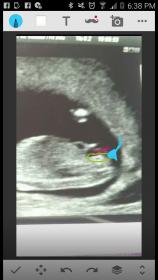

Can you post your pic without the drawing on please :)